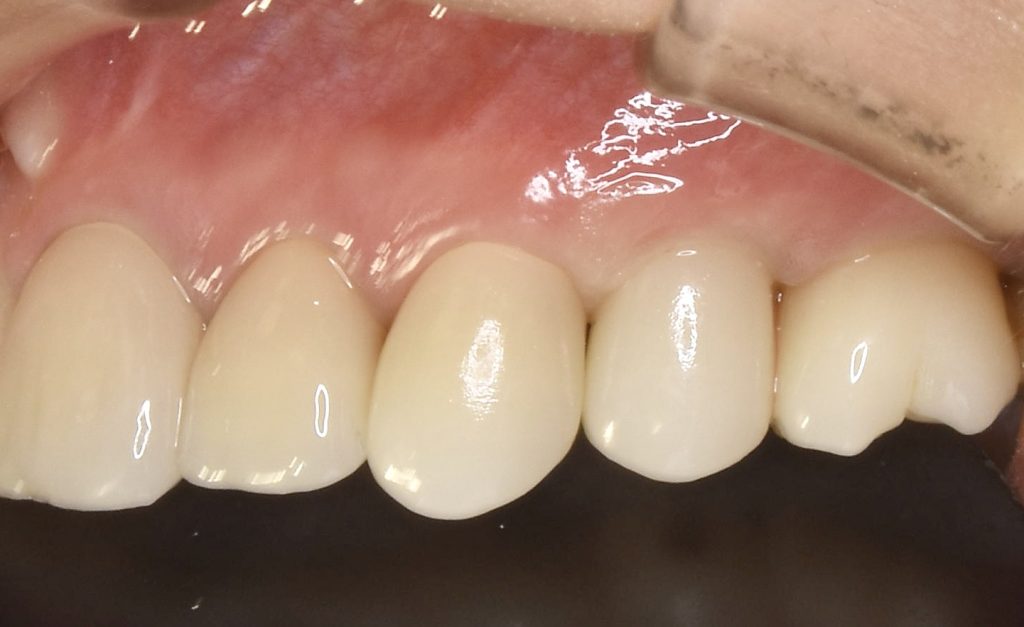

下記の症例は当院の審美領域のインプラント治療の治療結果となります。

治療後、どの歯を抜歯してインプラント治療を行ったか見分けがつかないような治療結果に拘っています。

治療後のクオリティーはもちろん、できるだけ負担の少ない術式を意識し、患者ファーストを第一に考えております。

この症例に発生する費用 約85万円(税抜)